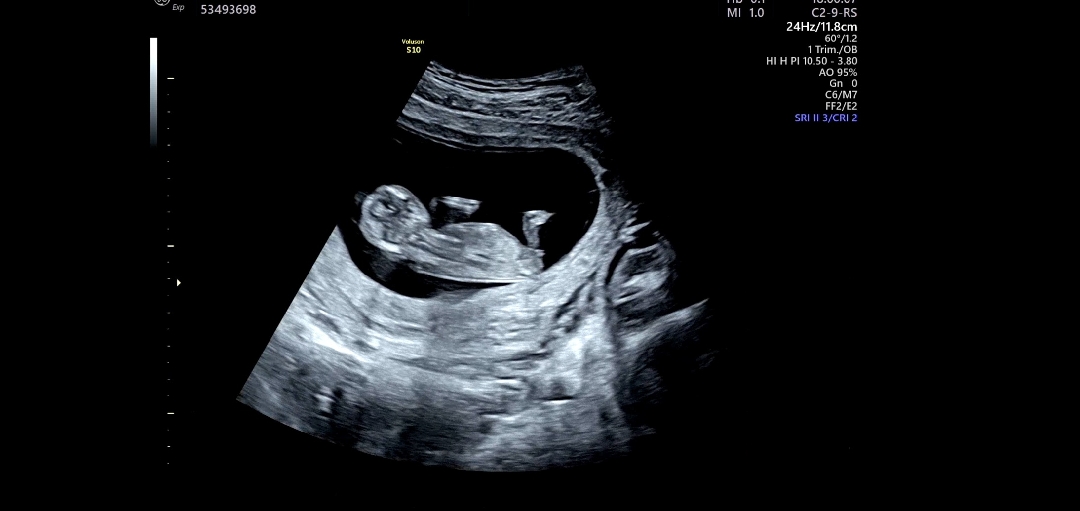

지피티는 위 사진 기준 80-85프로 남아라고 하네요!

딸일까요!? 한번만 봐주세요 부탁드려요ㅠㅠ